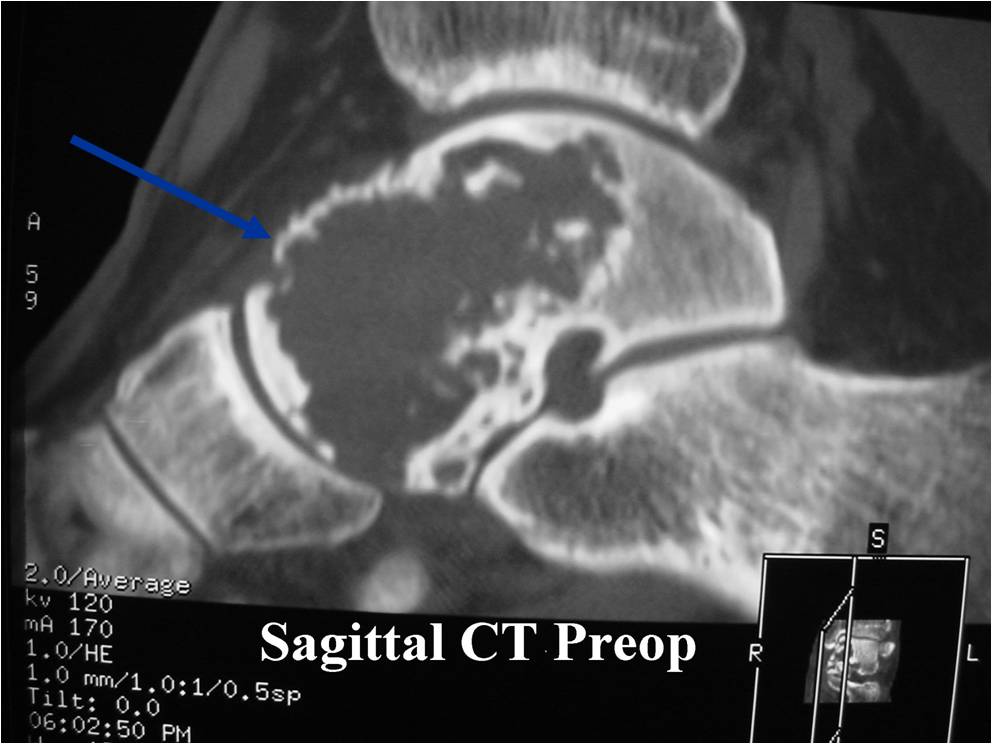

- (CT appearance)

- Most useful for detecting subtle mineralization not apparent on X-rays

- Useful for identifying intact periosteum around any expansile soft tissue component

- surrounding thin reactive shell of bone/mineralization (Egg Shell Rim of Calcification)

- helps place the tumor in a benign category

- helps evaluate:

- bony quality

- extent of bone and cortical destruction

- whether the subchondral plate of bone adjacent to the articular cartilage has been destroyed or is intact

- Calcifications are often better detected with a CT scan but are not uniformly present

- Often better detected with a CT Scan